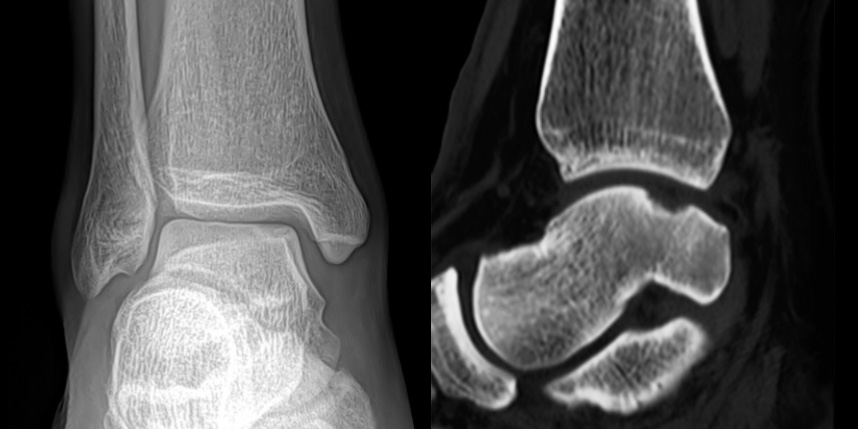

환자 자신의 건강한 연골을 채취하여 손상된 부위에 이식하는 방법으로, 발목 연골 손상에 주로 이용하며 정상 연골을 채취해야 하기 때문에 공여부(donor site)의 문제가 있을 수 있다는 점이 최대 단점입니다.

타병원 미세천공술 실패 후 통증으로 내원하신 사례

* 환자에게 받은 소중한 자료입니다.